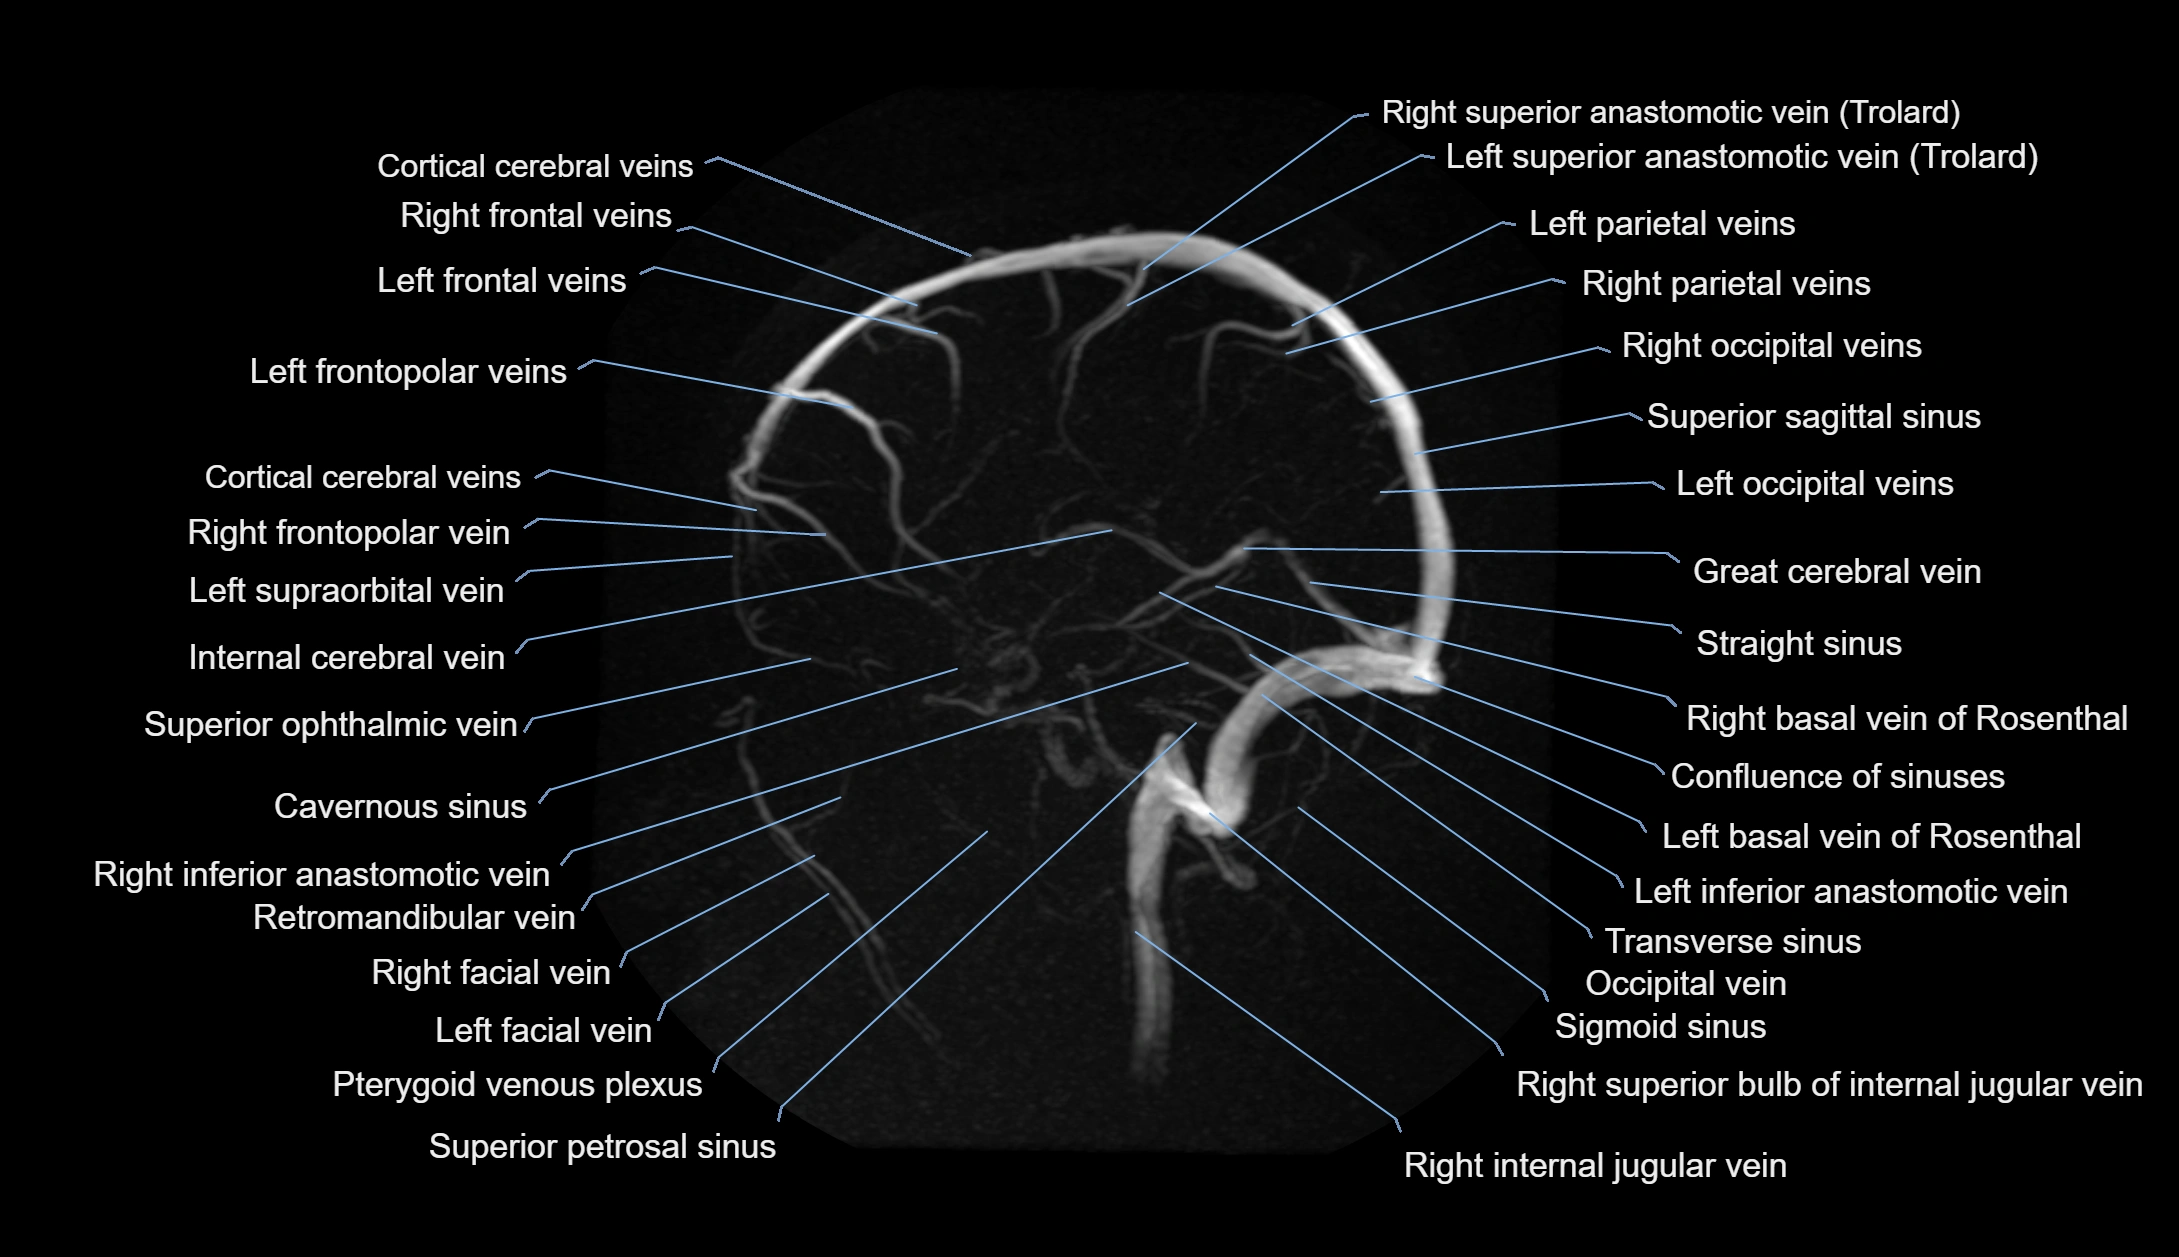

MRI images

image